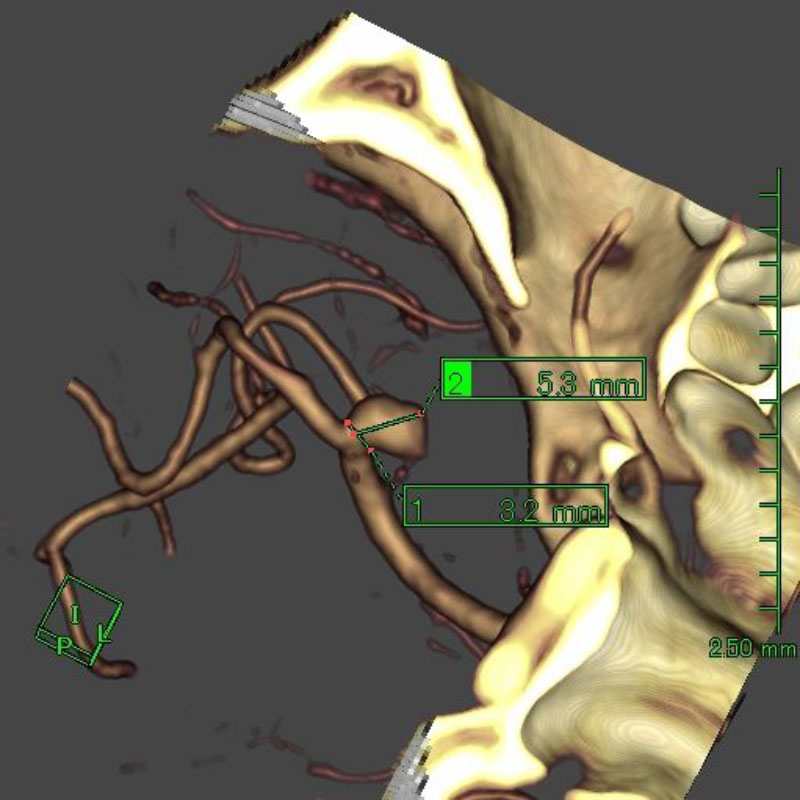

※ 画像をクリックすると拡大表示します。症例No.をクリックすると詳細ページを表示します。

手術前

クリップ前

クリップ後

手術後